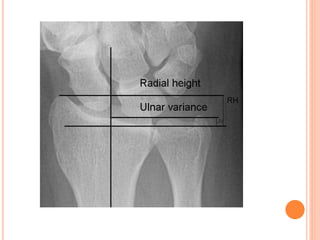

X-RAY EVALUATION OF DRUJ

a)True PA views should

show the groove for

ECU radial to the ulnar

styloid (red arrow). True

lateral view should show

the palmar edge of

pisiform (red dotted line)

midway between palmar

borders of distal pole of

scaphoid and capitate

(yellow lines);

(b) Scheker-weighted

lateral view with patient

holding 3 lb weight in the

hand showing dorsal

instability of the distal

ulna. Weighted views

provide loading of the

DRUJ, bringing out

instability, which may not

be visible in routine X-

rays